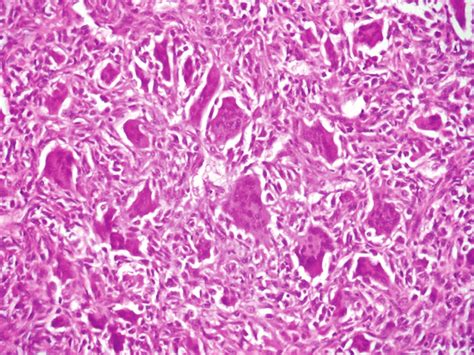

-Microscopia (aumento 100×). Observa-se neoplasia constituída por